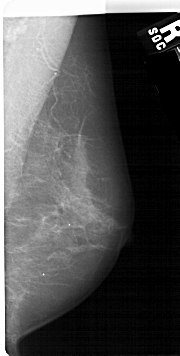

Digital Database for Screening Mammography

Volume: benign_07 Case: A-1686-1

A_1686_1.RIGHT_MLO

RIGHT_CC LINES 5191 PIXELS_PER_LINE 2251 BITS_PER_PIXEL 12 RESOLUTION 43.5 NON_OVERLAY

FILE: A_1686_1.LEFT_CC.OVERLAY

TOTAL_ABNORMALITIES 1

ABNORMALITY 1

LESION_TYPE MASS SHAPE IRREGULAR MARGINS ILL_DEFINED

ASSESSMENT 4

SUBTLETY 3

PATHOLOGY BENIGN

TOTAL_OUTLINES 1

BOUNDARY